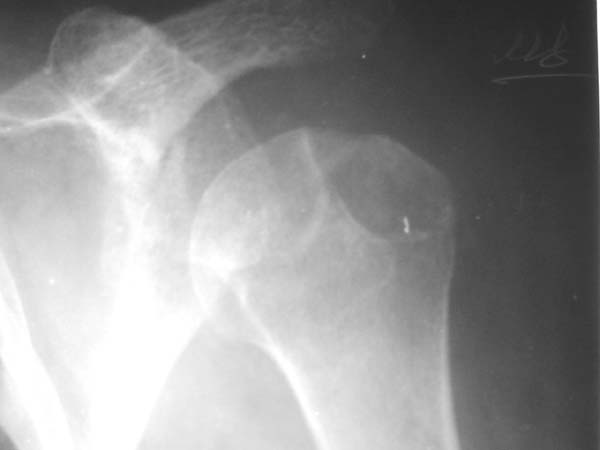

Уважаемые коллеги!Женщина, 60 лет. 3 недели назад упала с упором на отведенную левую руку. Почувствовала боль в левом плечевом суставе. За помощью не обращалась. 2 недели "мази и припарки". Затем - рентгенограмма (r1 и r2), жалобы на боли,ограничение движений...

Активное отведение 80 гр., при пальпации - головка плечевой кости безболезненно вправляется и тут же самостоятельно вывихивается. Наложена косыночная иммобилизация, рентгенография (r3) и МРТ.В нашем диагностическом центре МРТ исследование плечевого сустава выполнено впервые, опыта у нас маловато :(.Вопросы: уточнение диагноза? какие исследования провести? тактика лечения?

Как Вам известно, в некоторых случаях вывихи плеча сопровождаются разрывом ротаторной манжетки, отрывному перелому большого бугорка что приводит к потере наружной ротации и отведения плеча. На представленных рентгенограммах перелом не виден.

МРТ должен показать разрыв манжетки, но признаться я не большой эксперт по чтению МРТ сканов, хотя затемнение, отек мягких тканей по задней поверхности плеча видны Обычные рентгенограммы демонстрируют остеолизис в области большого бугорка.

1. На рентгене - нижний подвывих плеча и очаг остеолиза суставного бугорка с четкими контурами (вдавленный перелом на фоне остеопороза ? доброкачественная опухоль? аваскулярный некроз ? (хотя ни разу не слышал об аваскулярном некрозе плеча..)

Судя по снимкам, речь идTт о типичном случае Hill-Sachs Lesion. По этому поводу я позволю себе некоторый экскурс:

97 % всех вывихов плеча происходит по механизму комбинации отведения, разгибания и наружной ротации (А. Гринспан). В момент вывиха головка плеча ударяет о нижний край гленоида, что ведет к вдавленному или компрессионному перелому одной или обеих структур. Чаще всего, однако, повреждение возникает в задней латеральной области головки плечевой кости на переходе от головки к шейке. Этот диагноз можно выставить на основании рентгеновского снимка в переднезадней проекции с внутренней ротацией плеча. Несколько реже видно повреждение гленоида о передненижний перелом края. То, что мы называем Bankart Lesion. Это повреждение видно на ре. снимке в п.з. проекции при нейтральной позиции плеча. Разумеется хрящевые и мягкотканные повреждения (в смысле Банкарт) мы увидим лучше всего на ЯМР.

Учитывая описанную клинику, речь идTт о комбинации патологии. К сожалению, учитывая качество снимков NMR, я не могу провести достаточно точную верификацию состояния нижнего края гленоида, что впрочем, не меняет рекомендации. Для определения состояния РМ и дополнить исследование УЗИ мягких тканей плеча. В опытных руках достаточно информативное и дешевое исследование.